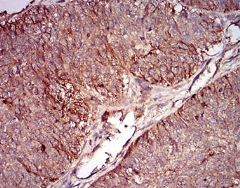

IHC    1/200 - 1/1000